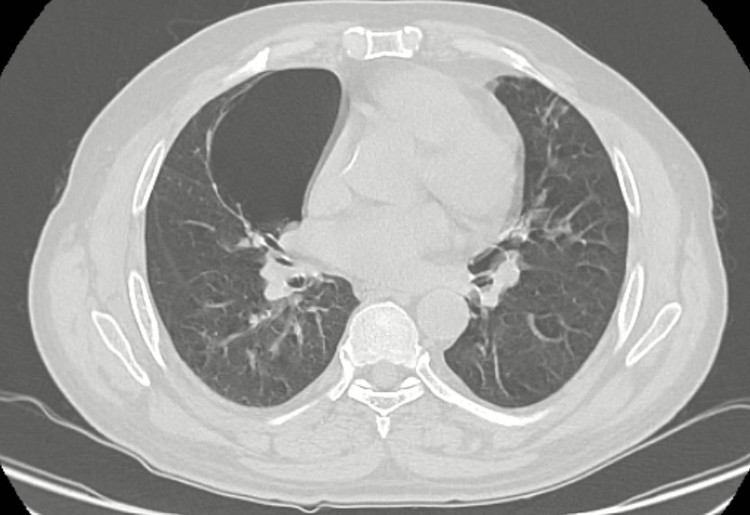

Kết quả chụp CT Scanner ngực có hình ảnh đám đông đặc phân thùy lưỡi phổi trái, dày tổ chức kẽ hai phổi, bóng khí thùy giữa phổi phải kích thước 59x90mm. Các bác sĩ đã hội chẩn kết luận kén khí lớn thùy giữa phổi phải trên nền bệnh nhân hen phế quản, bệnh phổi tắc nghẽn mạn tính, đái tháo đường tuyp II.

| Kén khí phổi trên phim chụp của bệnh nhân |